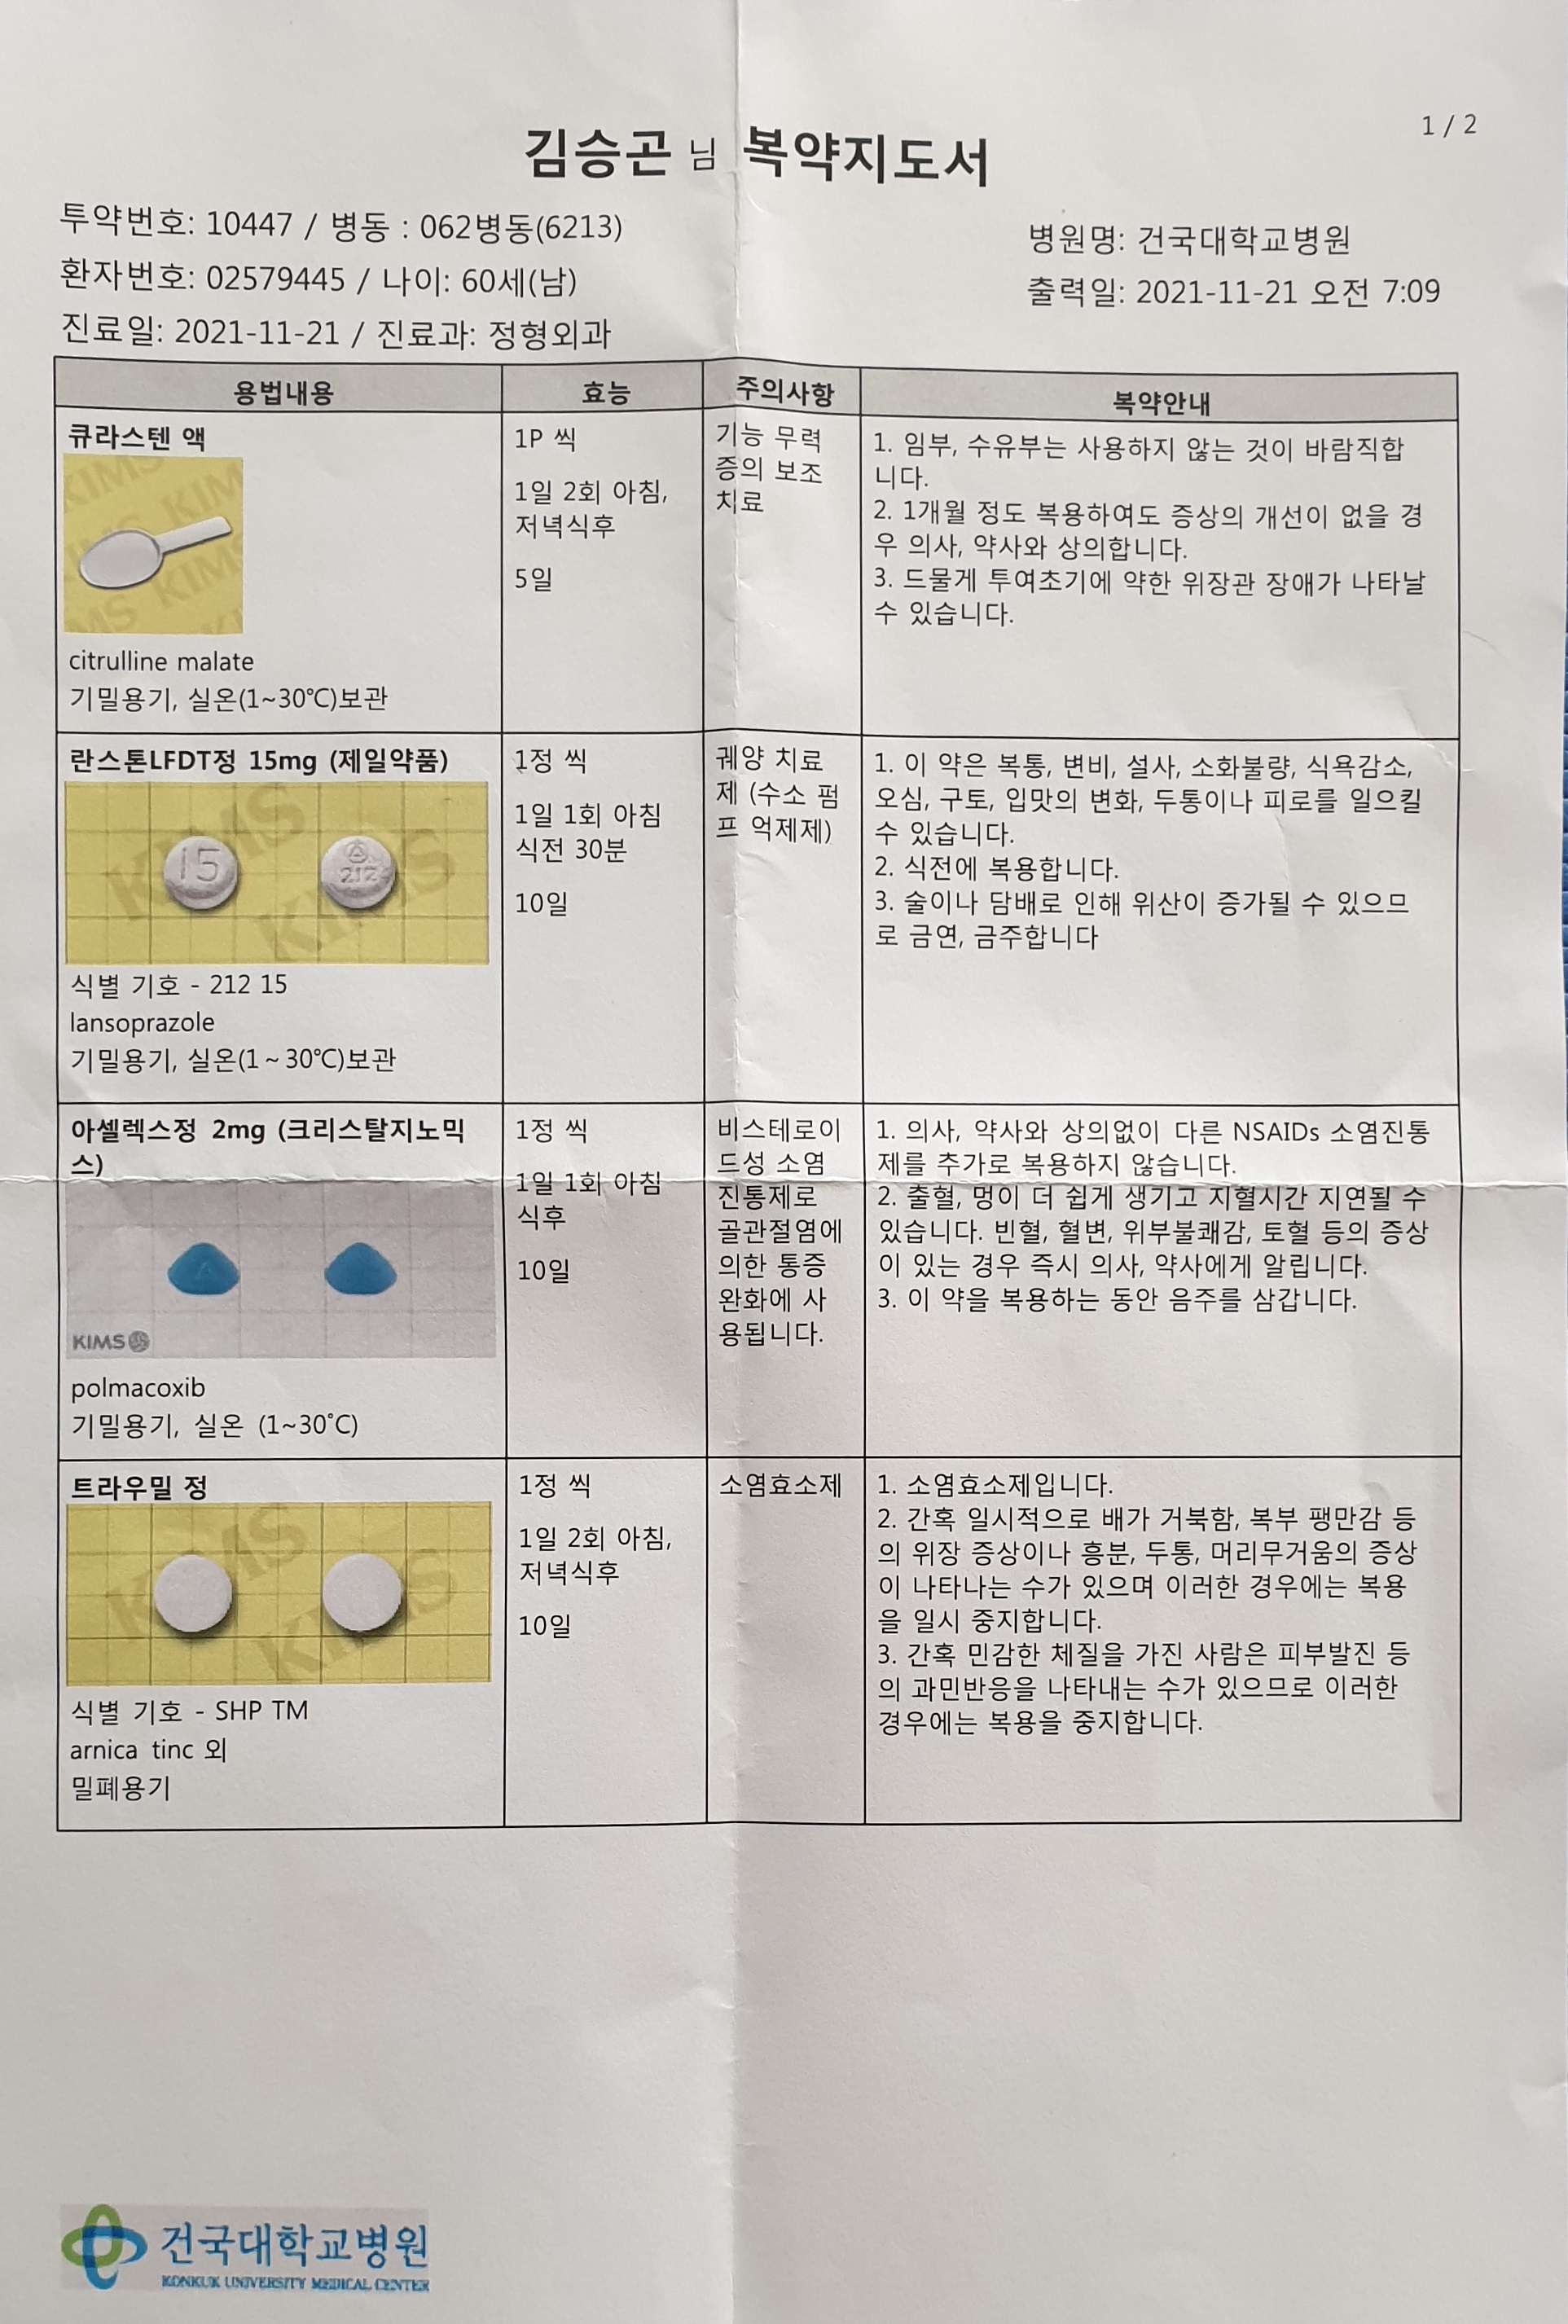

발목에 떨어져 나간 연골은 빼내고 거골에 미세 천공을 하여 골수가 나오도록 만들어야 하는데 한달동안 기부스에 꼼작 말아야 한다는 소견이다.

내시경 수술로 파열돤 연골을 빼내는것이야 1박 2일정도면 쉽게 끝난다 하지만 관절염은 평생을 갈수 있다고 한다.

정형외과에서 발목을 치료를 한다.

퇴원 치료라고....

그리고 수술할때 차고 있던 가부스를 벗겨버리고 VACO ped를 신겨준다.

비싼거라며

그리고 나중에 다 낳거던 중고시장에 팔아라는 귀뚬까지 한다.